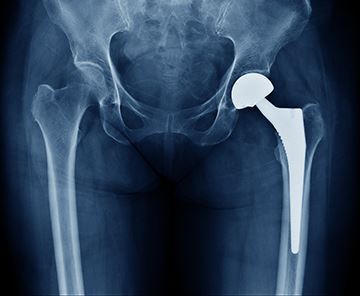

The vast majority of medical devices are approved by the FDA but have undergone little if any clinical testing.

In just the last ten years alone, medical devices have caused almost two-million injuries and more than 80,000 deaths.

“There have been metal hips that released poisonous debris into the body, implantable defibrillators that shock people at random (causing indescribable terror) and artificial heart valves with questionable shelf lives. In operating rooms, there have been staplers that misfire; temperature control machines that spray bacteria into open chest cavities; and robotic surgeons that slap, burn and, in some cases, maim patients.”